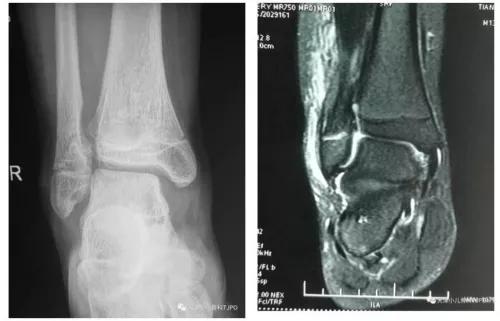

13岁,男,右外踝骨折史约1年余,今扭伤来诊,右外踝压痛,无明显肿胀。X线未见明显骨折,MRI可见外踝骺板高信号。

11岁,男,扭伤来诊外踝肿胀压痛;X线可见外踝肿胀影,未见明显骨折;MRI示外踝2型骺损伤。